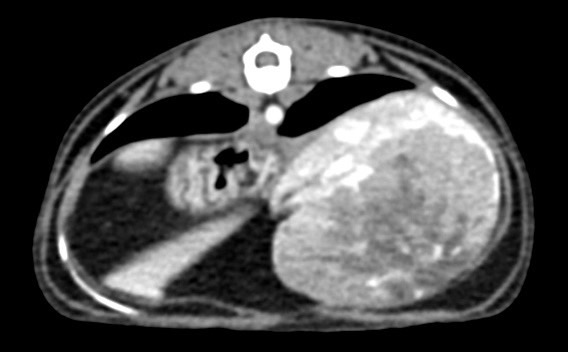

腹腔團塊採樣、術前評估、治療計畫擬定

肝臟團塊,評估範圍、手術可行性、肝臟採樣